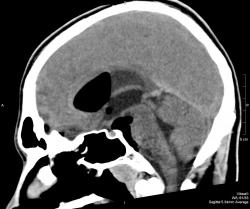

На снимках виден большой костный дефект (желтая стрелка) в задней стенке лобной пазухи, в полости черепа воздух, который прослеживается в области дефекта в полюсе лобной доли, в большой порэнцефалической кисте с уровнем жидкость-воздух (красные стрелки). Киста связана в передним рогом бокового желудочка, в противоположном желудочке и в третьем воздух (зеленые стрелки). На сагиттальных срезах виден воздух в мостовой цистерне вдоль ската. Поскольку дефект довольно большой, сейчас решается вопрос как лучше его закрыть эндоскопически или через трепанацию.